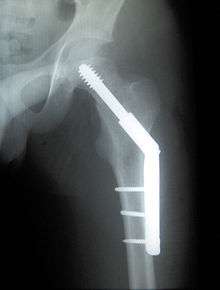

Intertrochanteric fracture

An intertrochanteric fracture, below the neck of the femur, has a good chance of healing. Treatment involves stabilizing the fracture with a lag screw and plate device to hold the two fragments in position. A large screw is inserted into the femoral head, crossing through the fracture; the plate runs down the shaft of the femur, with smaller screws securing it in place.

The fracture typically takes 3–6 months to heal. As it is only common in elderly, removal of the dynamic hip screw is usually not recommended to avoid unnecessary risk of second operation and the increased risk of re-fracture after implant removal. The most common cause for hip fractures in the elderly is osteoporosis; if this is the case, treatment of the osteoporosis can well reduce the risk of further fracture. Only young patients tend to consider having it removed; the implant may function as a stress riser, increasing the risk of a break if another accident occurs.